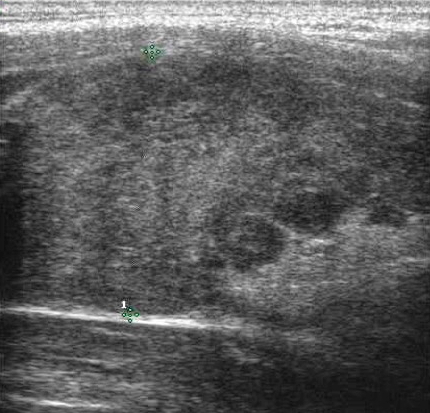

L’ipoecogenicità è dovuta all’aumento della quota cellulare rispetto alla colloide. Una marcata ipoecogenicità (simile a quella dei muscoli pre-tiroidei) è associata ad aumento del rischio di malignità con elevata specificità (fig. 10); talvolta può essere difficile distinguerla dall’ecogenicità di una raccolta liquida densa, ma l'uso del Doppler e i cambiamenti di posizione sono dirimenti nei casi dubbi. È importante differenziarla dalla debole ipoecogenicità (valutata rispetto al parenchima tiroideo circostante), perché questa è comune tanto alla patologia maligna che benigna e ha una minore accuratezza diagnostica (fig. 11).

Figura 10. Nodulo tiroideo marcatamente ipoecogeno a margini regolari in sede para-carotidea. In caso di marcata ipoecogenicità può essere difficile distinguere un nodulo solido da una raccolta liquida densa. L'uso dell'ecodoppler e i cambiamenti di posizione sono dirimenti nei casi dubbi.